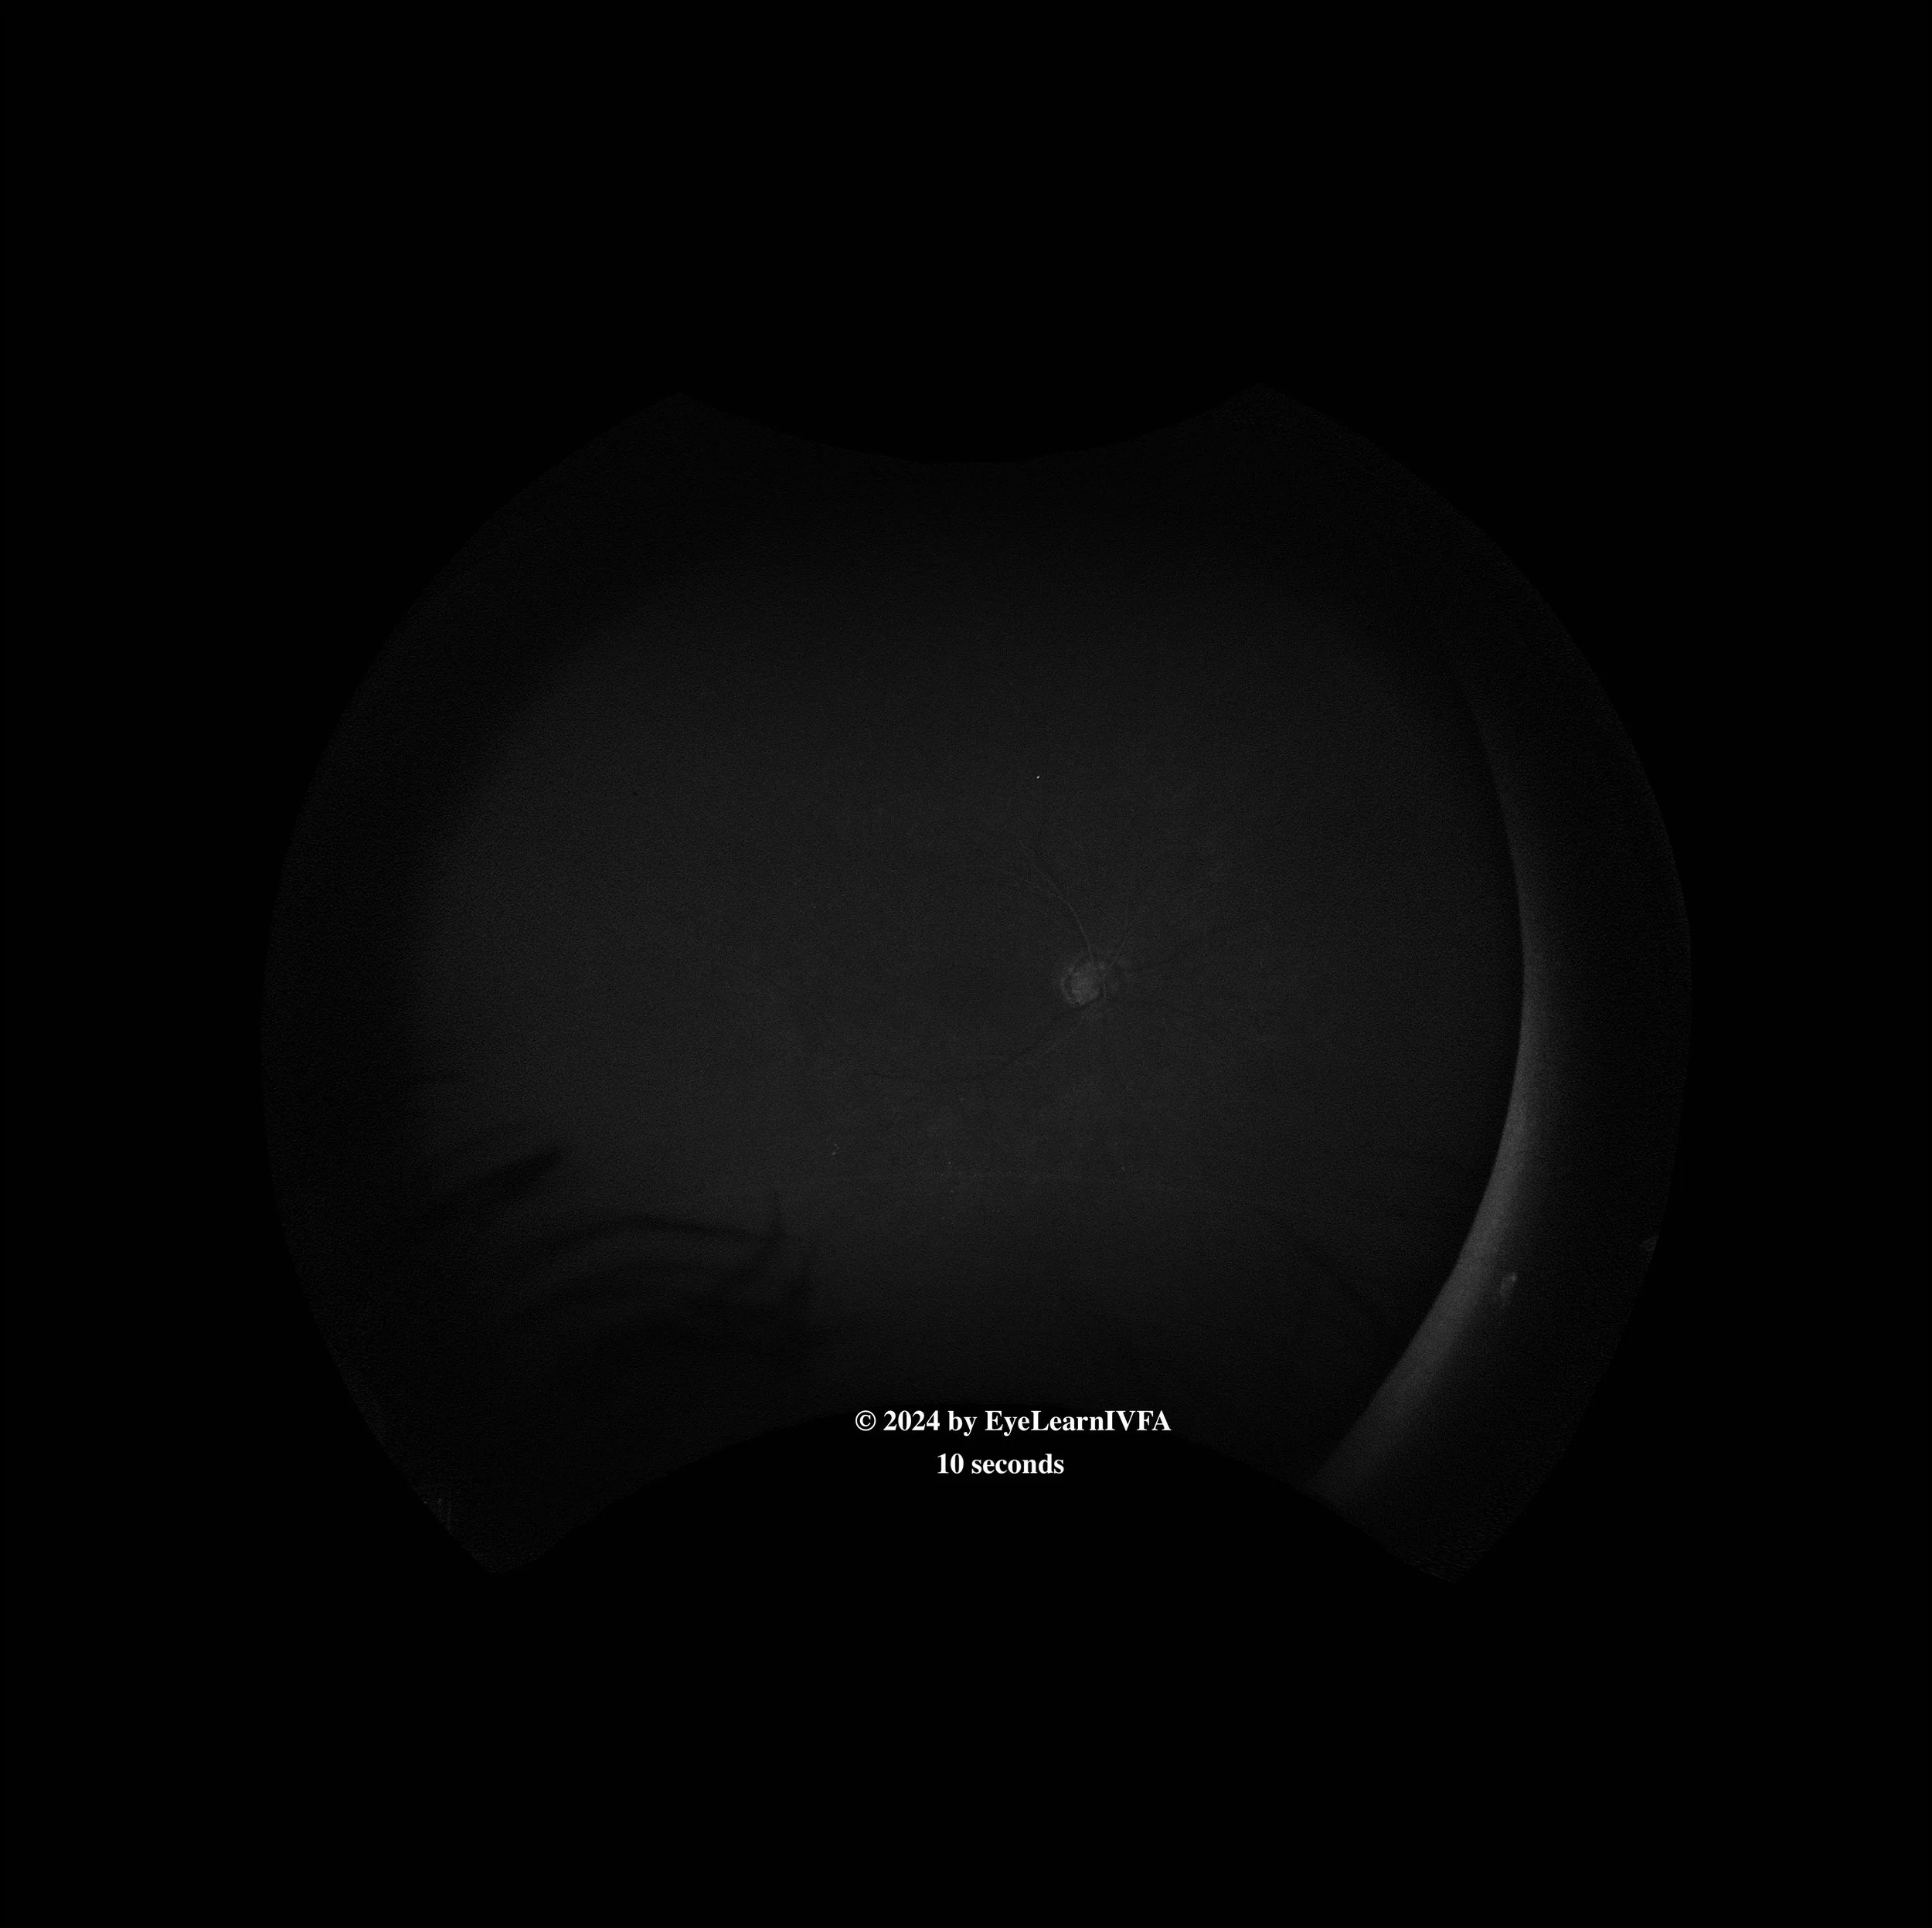

• IVFA at 10 seconds

Choroidal phase (early arterial)

Key features include:

• Absence of dye in retinal vessels

• Faint choroidal flush with patchy appearance of choroid. May be delayed in the context of retinal ischemia.